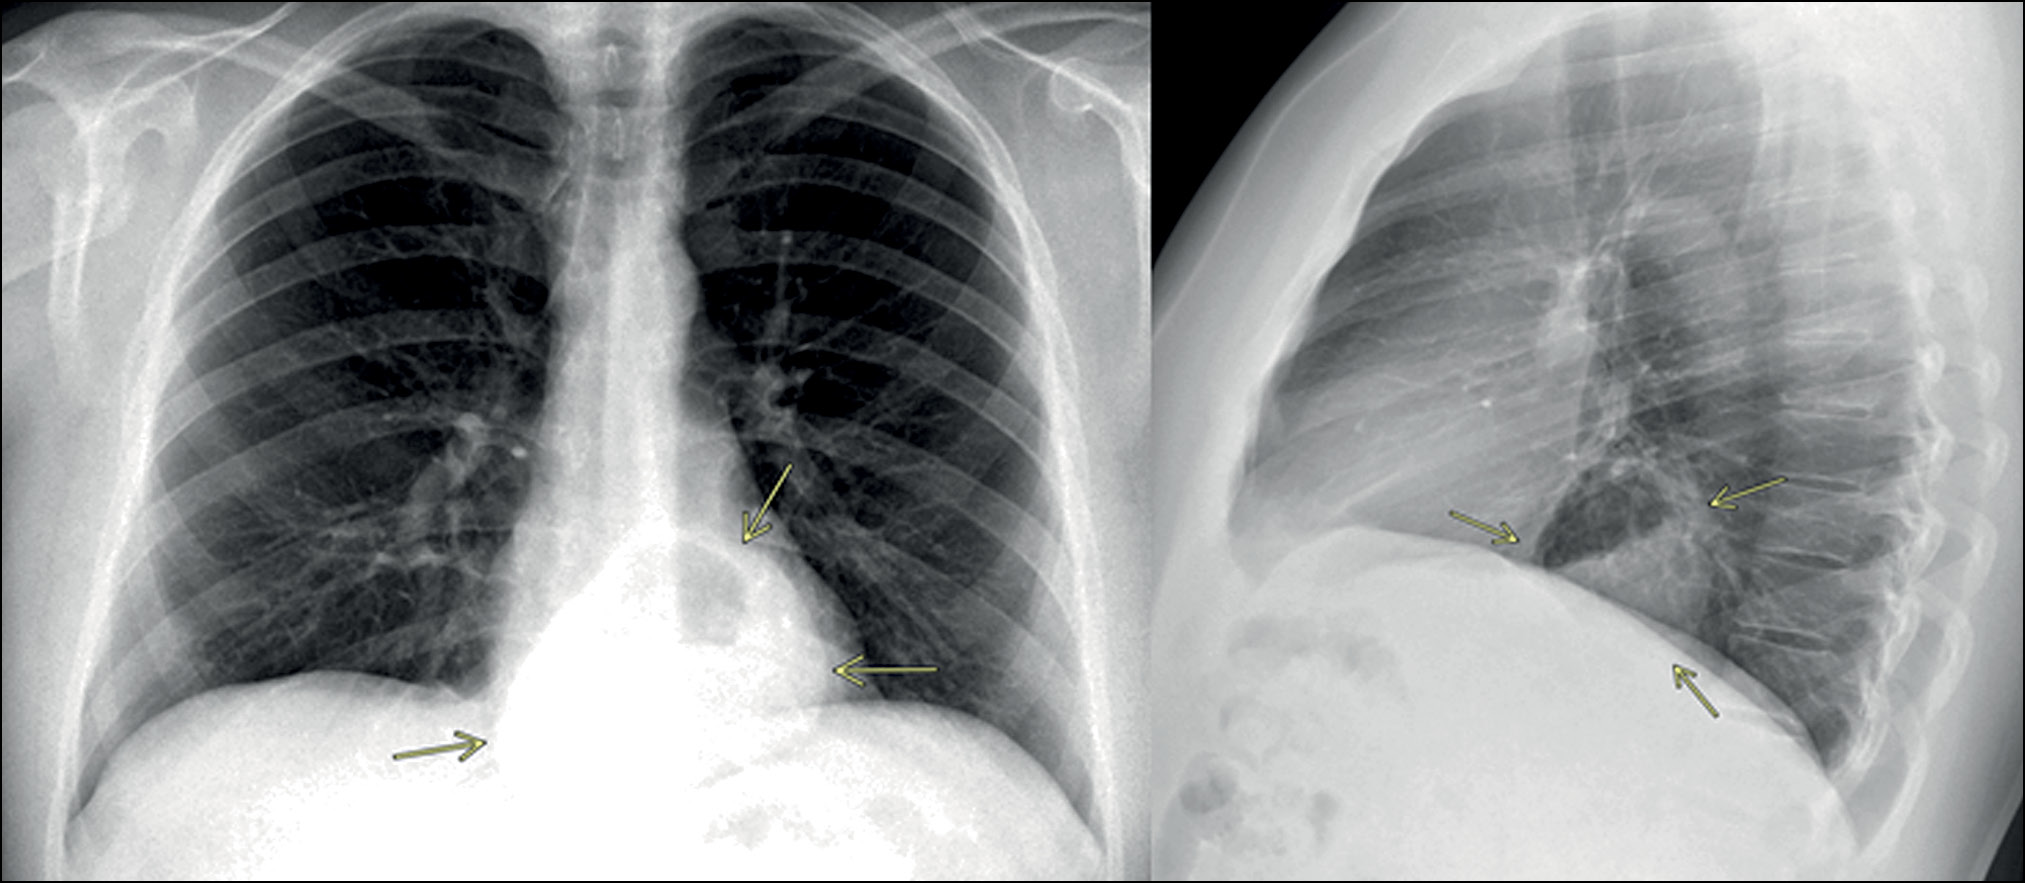

Проблемным вопросом диагностики при рентгенографии органов грудной клетки остаётся оценка корней лёгких на предмет патологических изменений ввиду суммации теней лёгочных сосудов и бронхов, вероятности наличия в корнях лёгких дополнительных образований, теней увеличенных уплотнённых лимфатических узлов, небольших прикорневых инфильтративных процессов в паренхиме лёгких, и проч. [18, 24]. В настоящее время задача по всесторонней оценке корней лёгких превышает имеющиеся возможности ИИ-сервисов. В данном исследовании было выявлено 39 ложноотрицательных случаев срабатывания ПО на основе ТИИ, связанных с наличием кальцинатов в корнях лёгких, о которых упоминает врач-рентгенолог при описании снимка, 1 ложноотрицательный случай кальциноза аорты, 1 случай ложноположительного срабатывания, связанный с тем, что сервис ИИ обозначил сосуд корня лёгкого как объёмное образование и 1 случай принятия расширенных сосудов корня лёгкого за лёгочное затемнение.

Большое клиническое значение может приобрести применение ПО на основе ТИИ в ургентной практике [26–29] при физическом отсутствии квалифицированного врача-рентгенолога [30] для экстренной диагностики таких жизнеугрожающих состояний, как гидро- и пневмоторакс [28, 31], и принятия клиницистом решения о необходимости незамедлительной госпитализации пациента либо выполнения плевральной пункции.

В числе ложноотрицательных случаев в рамках данного исследования было выявлено 2 случая, когда ПО на основе ТИИ не выявило наличие гидроторакса у лежачих пациентов (рис. 10), 1 случай невыявленного пневмоторакса у лежачего пациента. В то же время было выявлено 3 случая ложноположительного срабатывания, когда ИИ находил несуществующий пневмоторакс у лежачих пациентов. Данные находки несомненно требуют дообучения ПО на основе ТИИ для более эффективной работы с рентгенограммами, выполненными лежачим пациентам.

Рис. 10. Гидроторакс у лежачего пациента не был распознан программным обеспечением на основе технологий искусственного интеллекта.